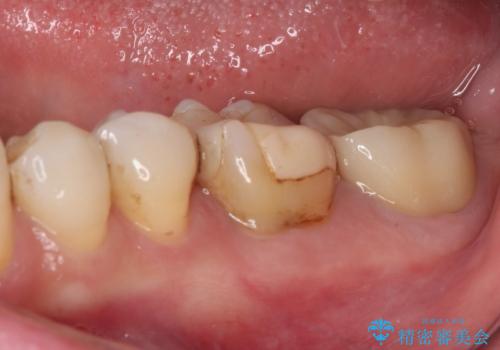

詰め物と歯に隙間ができており、既に根管治療をされた歯であったため、フルジルコニアクラウンにて補綴治療をすることとしました。

咬んだときに違和感があるとのことだったので、根管治療を事前におこなうこととしました。

仮歯を装着した時点でものが挟まる症状は改善されました。

根管治療により咬合時の違和感も解消されました。